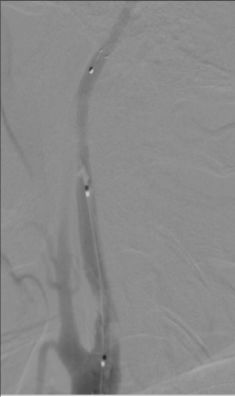

3. 颈内动脉C1段支架植入。

颈内动脉DSA提示颈内动脉狭窄,远端血流较差。 颈内动脉置入9mm-40mm Protege支架,收回保护伞后DSA提示血管再通良好,给予替罗非班7ml/h。 术后即刻查体NIHSS评分8分,给予替罗非班10ml/h泵入,持续24h。 术后第2天复查灌注成像提示双侧半球基本对称,CTA提示右侧颈内动脉以及大脑中动脉通畅。